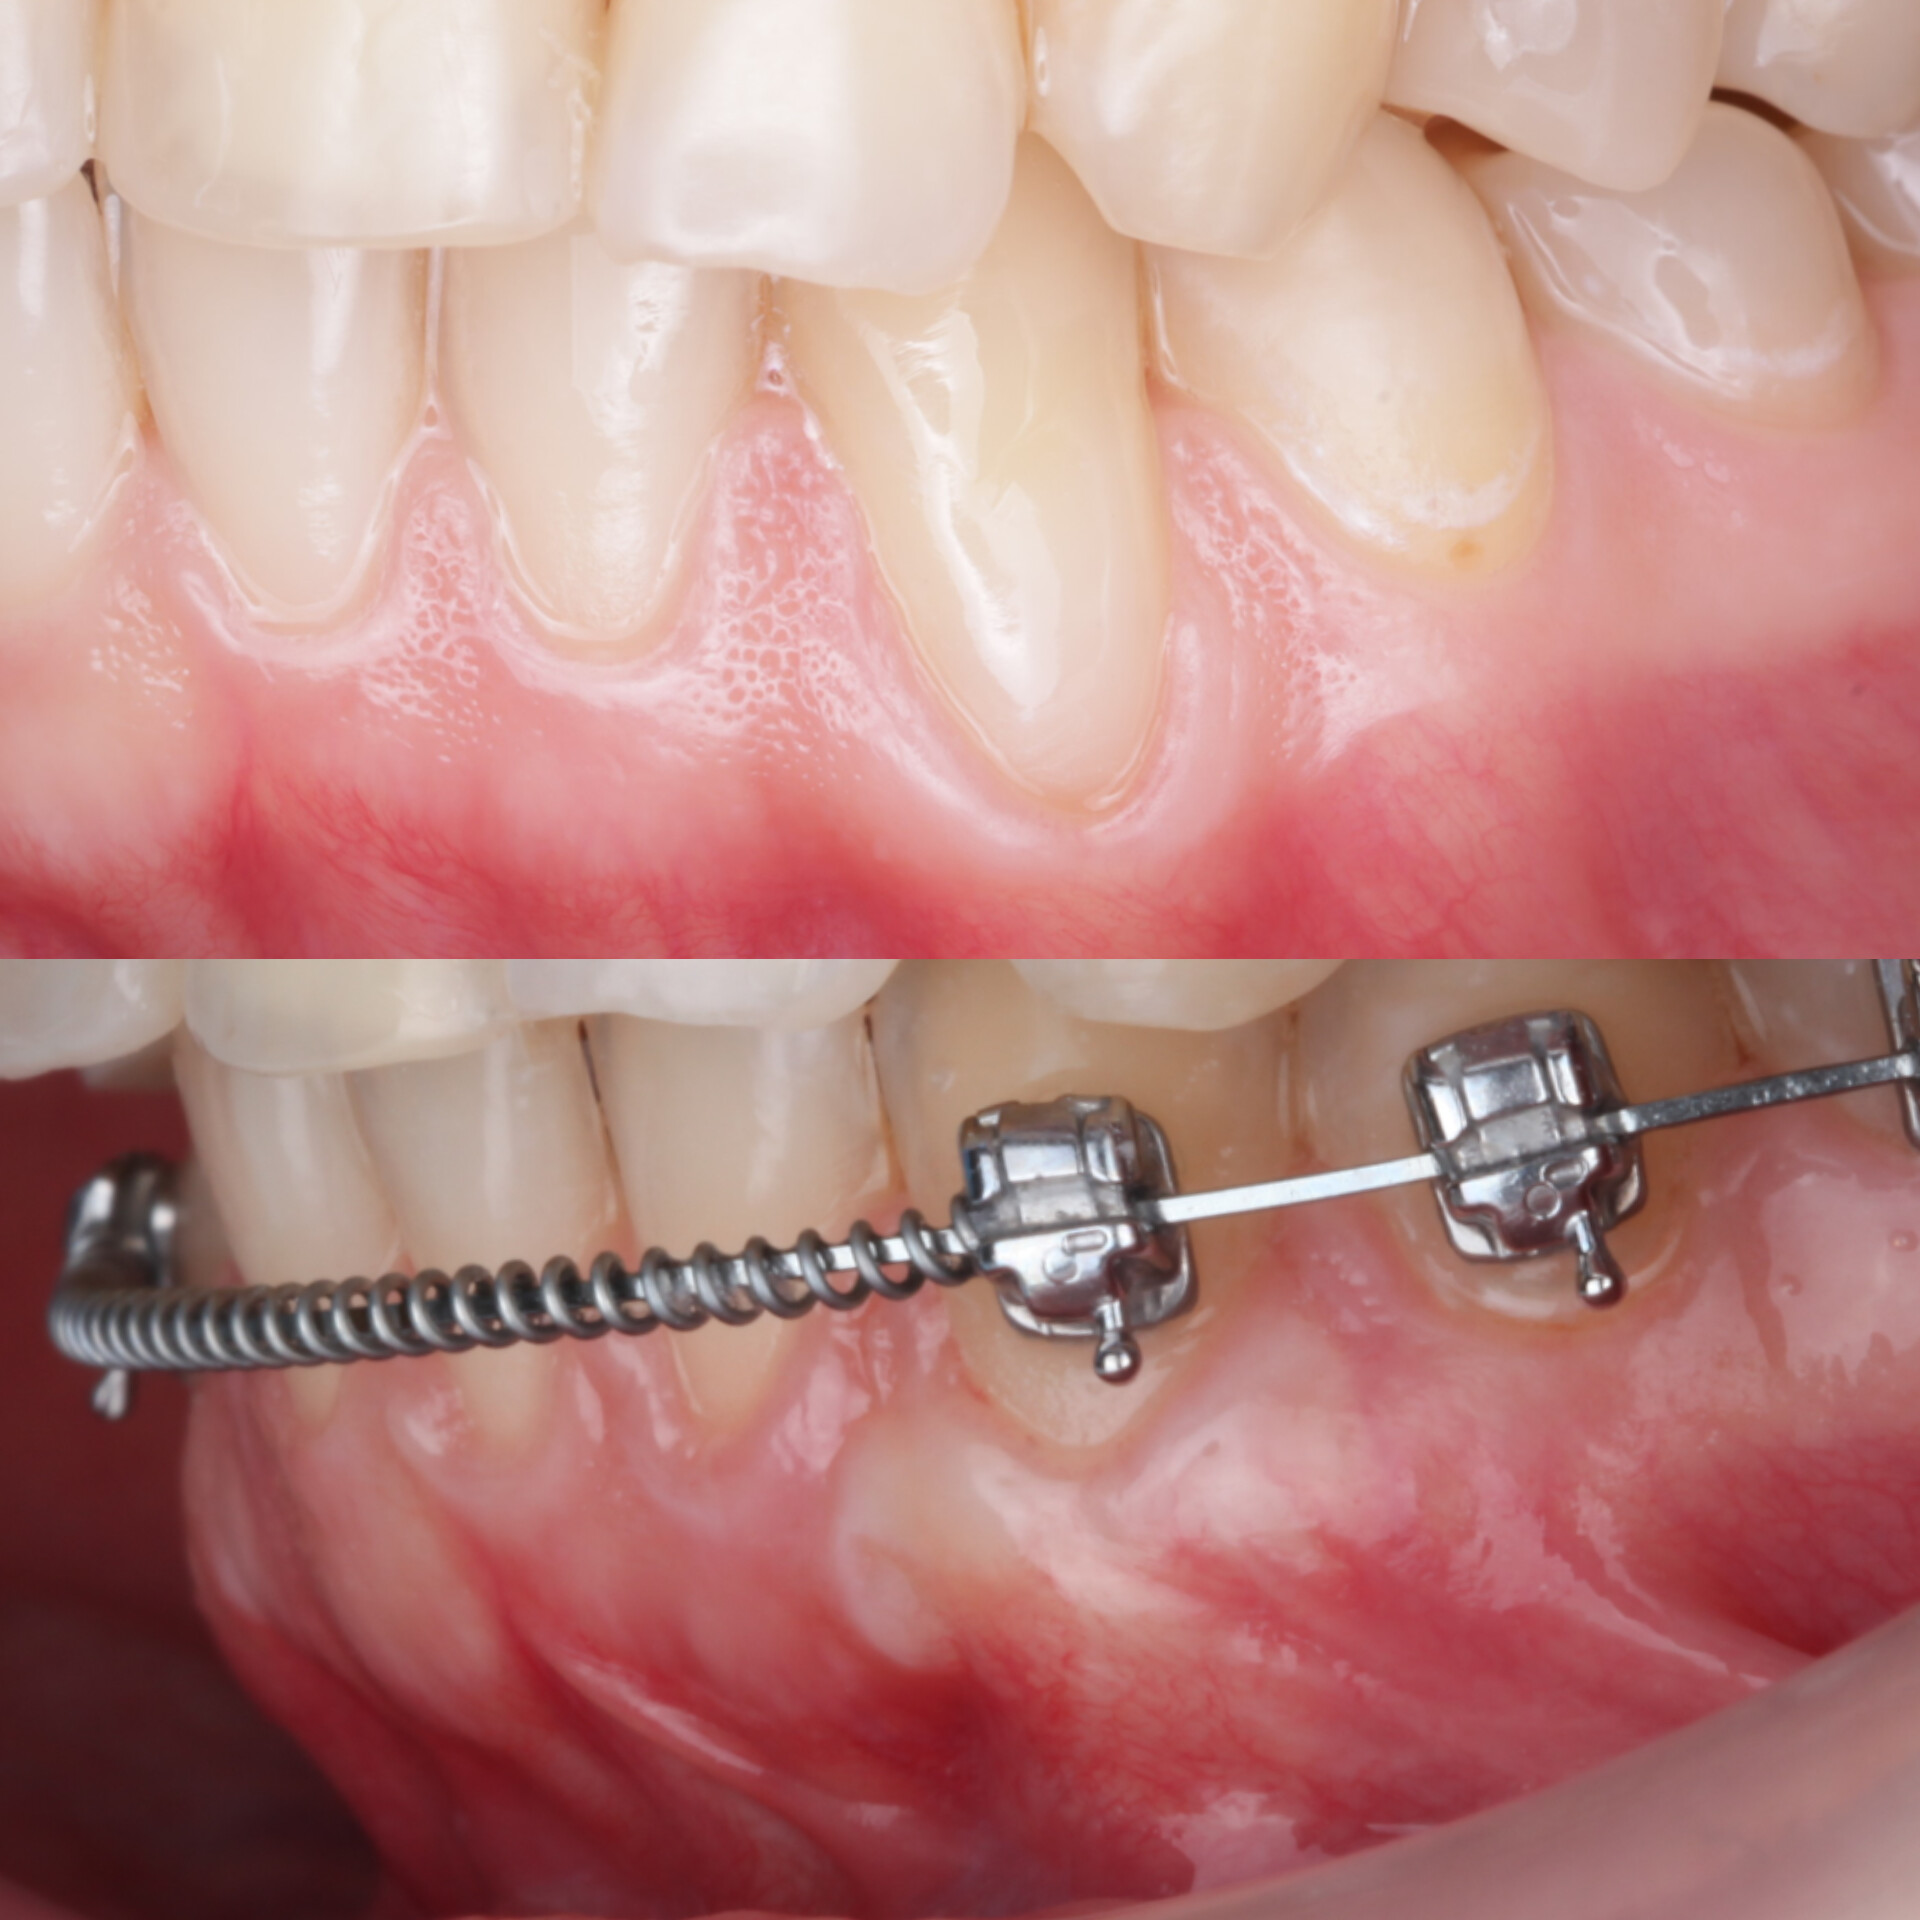

Спустя два месяца ортодонт зафиксировал брекеты. Мы видим полное закрытие рецессий и увеличение толщины десны. Это делает ортодонтическое лечение безопасным, а вероятность возникновения рецессий десны в дальнейшем — минимальной или практически невозможной

Осмотр спустя 6 месяцев :

Мы видим полное закрытие рецессий, увеличение толщины десны, что в дальнейшем делают ортодонтию безопасной, вероятность возникновения рецессий десны в дальнейшем минимальным или практически невозможным.